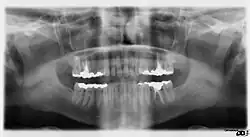

Минимально смещённый перелом правой нижней челюсти. Стрелка отмечает перелом, корневой канал на центральном резце, зубы слева от перелома не соприкасаются